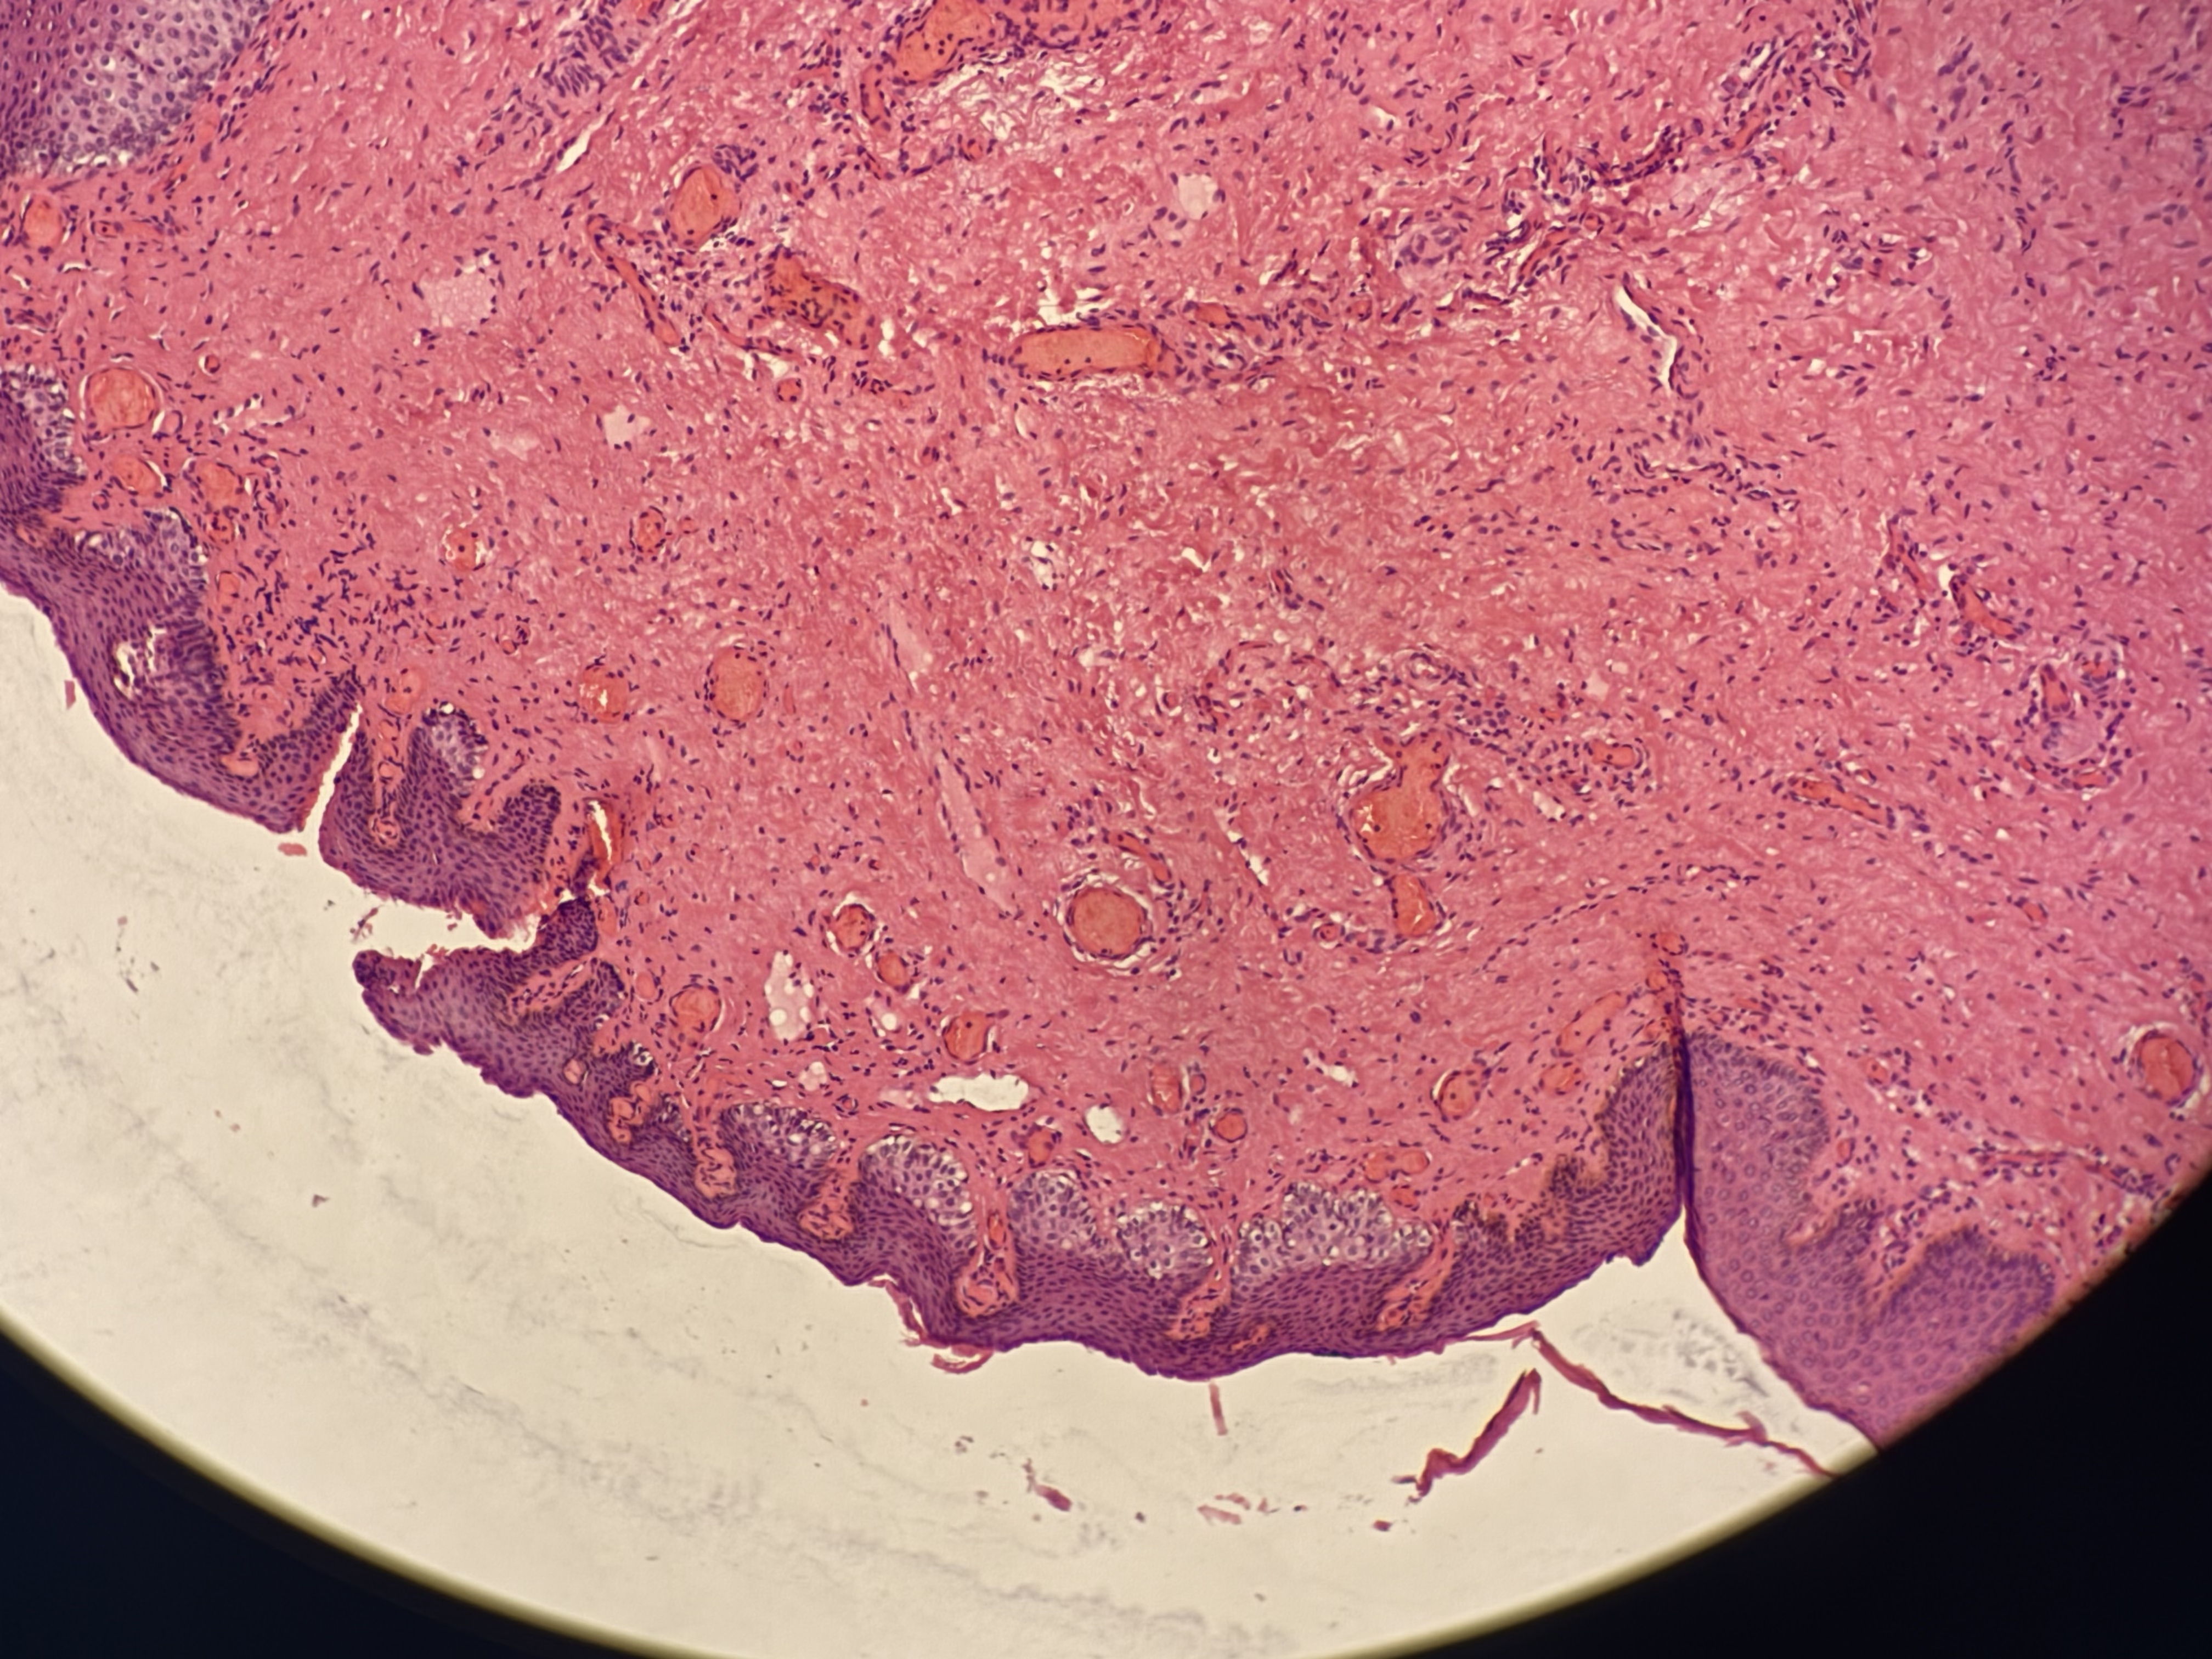

临床诊断痔疮,老师们帮忙看一下,谢谢

性别

女

年龄

17岁

临床诊断

混合痔

一般病史

无

标本名称

臀部混合痔

大体所见

灰红外痔软组织一块1x10.2cm

考虑符合:外痔伴鳞状上皮增生